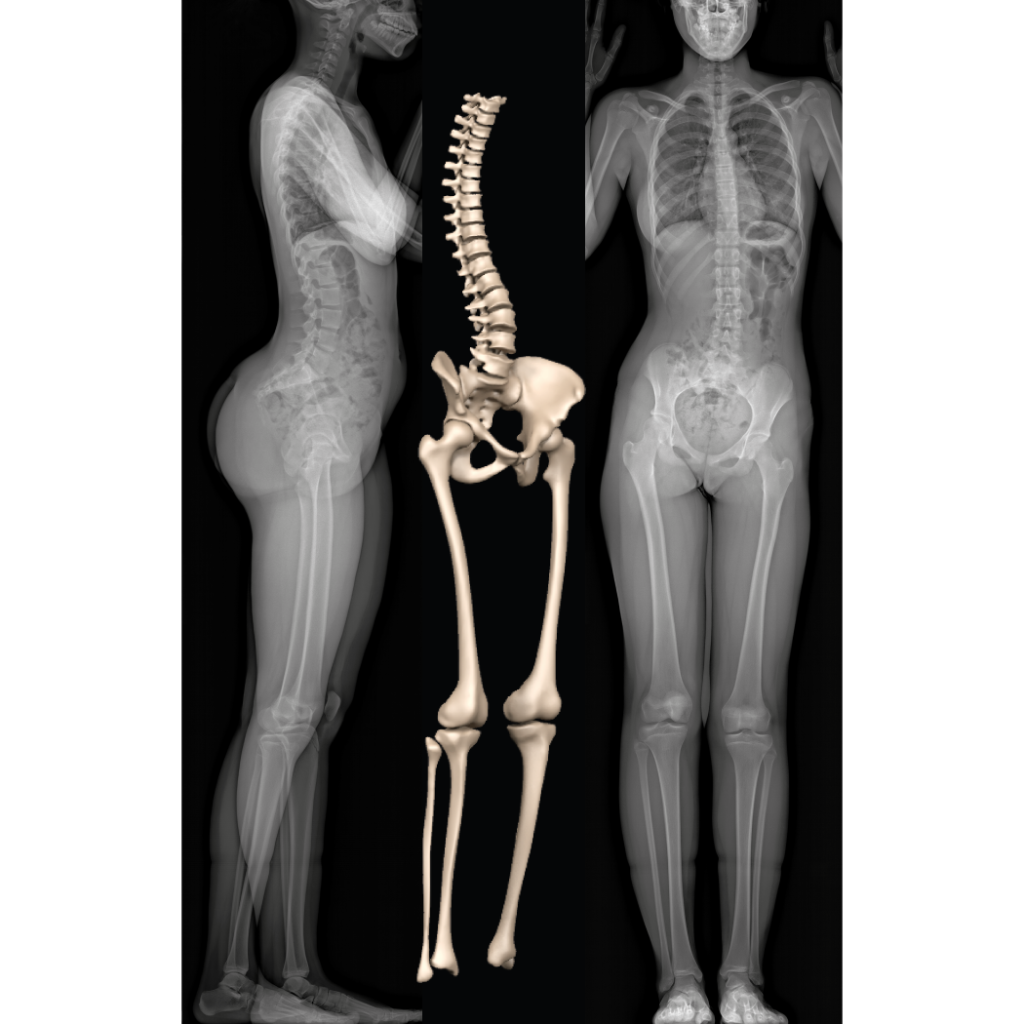

Système EOS – EOS imaging

Human Female Anatomy – Body Muscles Skelet… 3D Model .max .obj .3ds …

human female anatomy body 3d model

Xray, X-ray of the Human Female Body. Stock Illustration – Illustration …